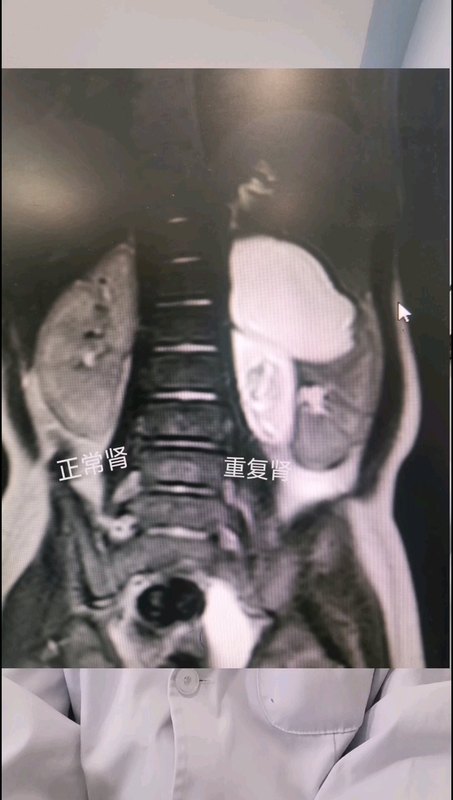

兒童重復(fù)腎畸形分為不完全型和完全型(圖1),臨床最為常見(jiàn)的是完全型,常見(jiàn)臨床癥狀是反復(fù)尿路感染,輸尿管反流和輸尿管囊腫是重復(fù)腎發(fā)生發(fā)熱性尿路感染的危險(xiǎn)因素。重復(fù)腎的治療方案我之前已經(jīng)發(fā)布過(guò)多個(gè)系列文章,目前的治療沒(méi)有統(tǒng)一的方案,更多的是需要視患兒個(gè)體情況制定個(gè)體化的診療方案。針對(duì)完全型重復(fù)腎伴上腎部輸尿管囊腫的治療方案里已經(jīng)發(fā)布的(https://station.haodf.com/health/article?healthId=8618720369&articleId=8445301567),輸尿管囊腫開(kāi)窗治療是其方案之一,但輸尿管囊腫開(kāi)窗術(shù)后部分會(huì)繼發(fā)輸尿管反流,從而需要再次手術(shù)行端側(cè)吻合(把反流的輸尿管吻合到下腎部沒(méi)有反流的輸尿管),因此我們提出了一種新的組合式治療策略就是在輸尿管囊腫開(kāi)窗的基礎(chǔ)上同時(shí)把輸尿管端側(cè)吻合手術(shù)做了(圖2),將完全型重復(fù)腎變成不完全型重復(fù)腎,這樣從根本上解決之前單一的治療策略導(dǎo)致的術(shù)后依然反復(fù)尿路問(wèn)題,手術(shù)效果良好,且絕大多數(shù)可以實(shí)現(xiàn)完全無(wú)管。當(dāng)然重復(fù)腎所有的治療方案里都不可避免的都有可能發(fā)生輸尿管殘端綜合征DUS(https://station.haodf.com/health/article?healthId=8618720369&articleId=4321090057),術(shù)后發(fā)生DUS的發(fā)病率約為0.8%~1%,取決于術(shù)前輸尿管形態(tài)、功能及遠(yuǎn)端有無(wú)梗阻、有無(wú)泌尿系感染和膀胱輸尿管反流等。通常情況下術(shù)后不會(huì)出現(xiàn)DUS,常見(jiàn)于術(shù)前反復(fù)發(fā)熱性尿路感染、膿腎患者。從我們臨床隨訪觀察結(jié)果看,術(shù)后效果明顯優(yōu)于單一的傳統(tǒng)治療方案,且不受年齡限制。